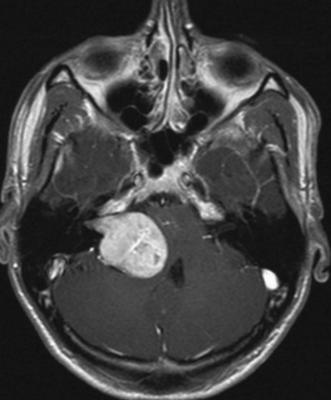

МРТ головы. Гиперинтенсивный сигнал в области сосцевидной пещеры, сосцевидного отростка и пирамиды правой височной кости (холестеатома)

Невринома слухового нерва на МРТ